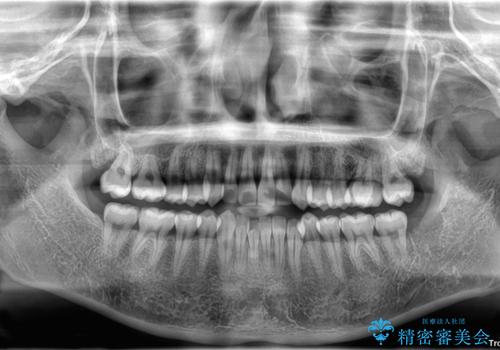

- 今回は「下の前歯のデコボコを治したい」と来院された患者様の症例をご紹介します。

診察してみると、下の前歯が並ぶためのスペースが足りないことが、歯並びがデコボコしている原因でした。

そこで今回は、以下の2つの方法を組み合わせて治療を行いました:

下の前歯の歯と歯の間をわずかに削ってスペースを作る(IPR)

奥歯を後ろに動かして、前歯が並ぶためのスペースを確保する

この計画により、デコボコだった下の前歯はしっかりと並び、わずか1年で治療を終えることができました